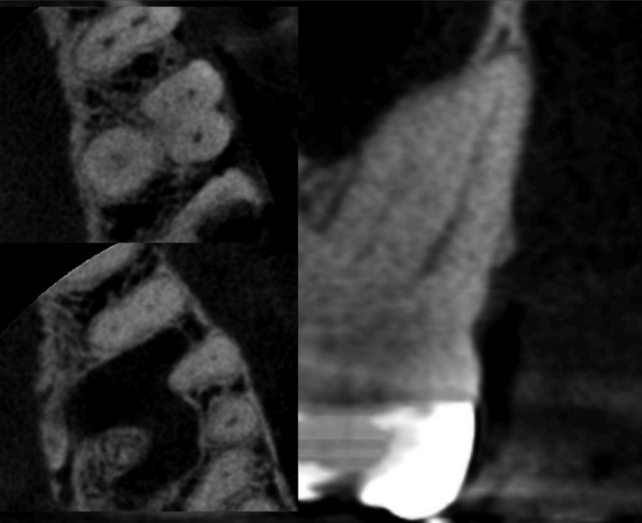

Рисунок 6 — Тип II (12,7%)

Рисунки 4–6 представляют корональные и аксиальные срезы КЛКТ для трех наиболее часто встречающихся типов анатомических конфигураций.